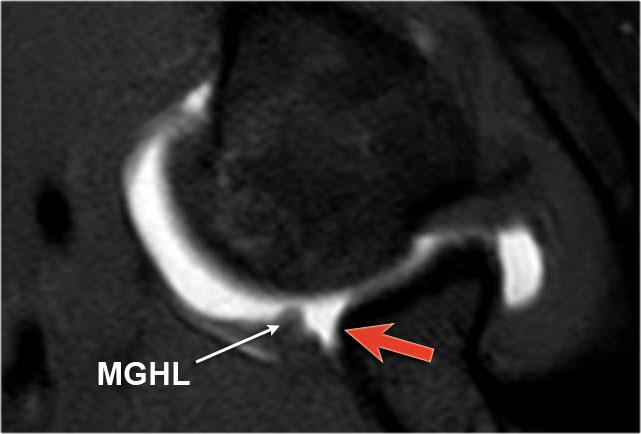

Tổn thương Perthes

Tổn thương Perthes là avulsion sụn viền-dây chằng tương tự Bankart, nhưng với màng xương bị bóc tách về phía trong mà vẫn còn nguyên vẹn.

Trên hình ảnh khớp vai ở tư thế trung gian, sụn viền bị rách có thể được giữ ở vị trí giải phẫu bình thường bởi màng xương bả vai còn nguyên vẹn, từ đó ngăn thuốc tương phản từ thấm vào đường rách.

Điều này có nghĩa là MRI khớp cản từ ở tư thế trung gian có thể không phát hiện được đường rách sụn viền.

Tuy nhiên, ở tư thế ABER, dây chằng ổ chảo-cánh tay dưới bó trước bị căng tạo lực kéo lên sụn viền trước-dưới, giúp tăng khả năng phát hiện đường rách.

Mũi tên chỉ vào màng xương còn nguyên vẹn.

Các hình ảnh ở tư thế ABER cho thấy sụn viền trước bị bong tách.

Hình bên phải được xoay 90° ngược chiều kim đồng hồ.

Đôi khi điều này giúp hiểu rõ hơn về giải phẫu.